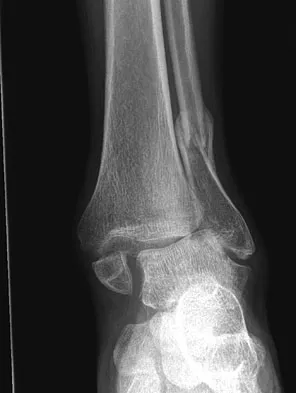

An obese 62-year-old man reports a 10-year history of progressive flatfoot deformity and a 3-month history of a painful callus along the plantar medial midfoot that has not improved with custom shoe wear, pedorthics, and callus care. There is no hindfoot motion, but functional ankle motion remains. He does not have diabetes mellitus. Radiographs are shown in Figures 27a and 27b. What is the best surgical option at this point?

Explanation

The deformity is long-standing, the hindfoot is immobile, and the radiographs reveal severe degenerative arthritis involving the entire hindfoot, severe deformity, and talonavicular dislocation. The "exostosis" responsible for the callus is the talar head; resection would severely destabilize the foot. Degenerative arthritis and fixed deformity preclude lateral column lengthening, medial slide calcaneal osteotomy, and talonavicular arthrodesis. Triple arthrodesis is the only viable option. Johnson JE, Yu JR: Arthrodesis techniques in the management of Stage II and III acquired adult flatfoot deformity. Instr Course Lect 2006;55:531-542.